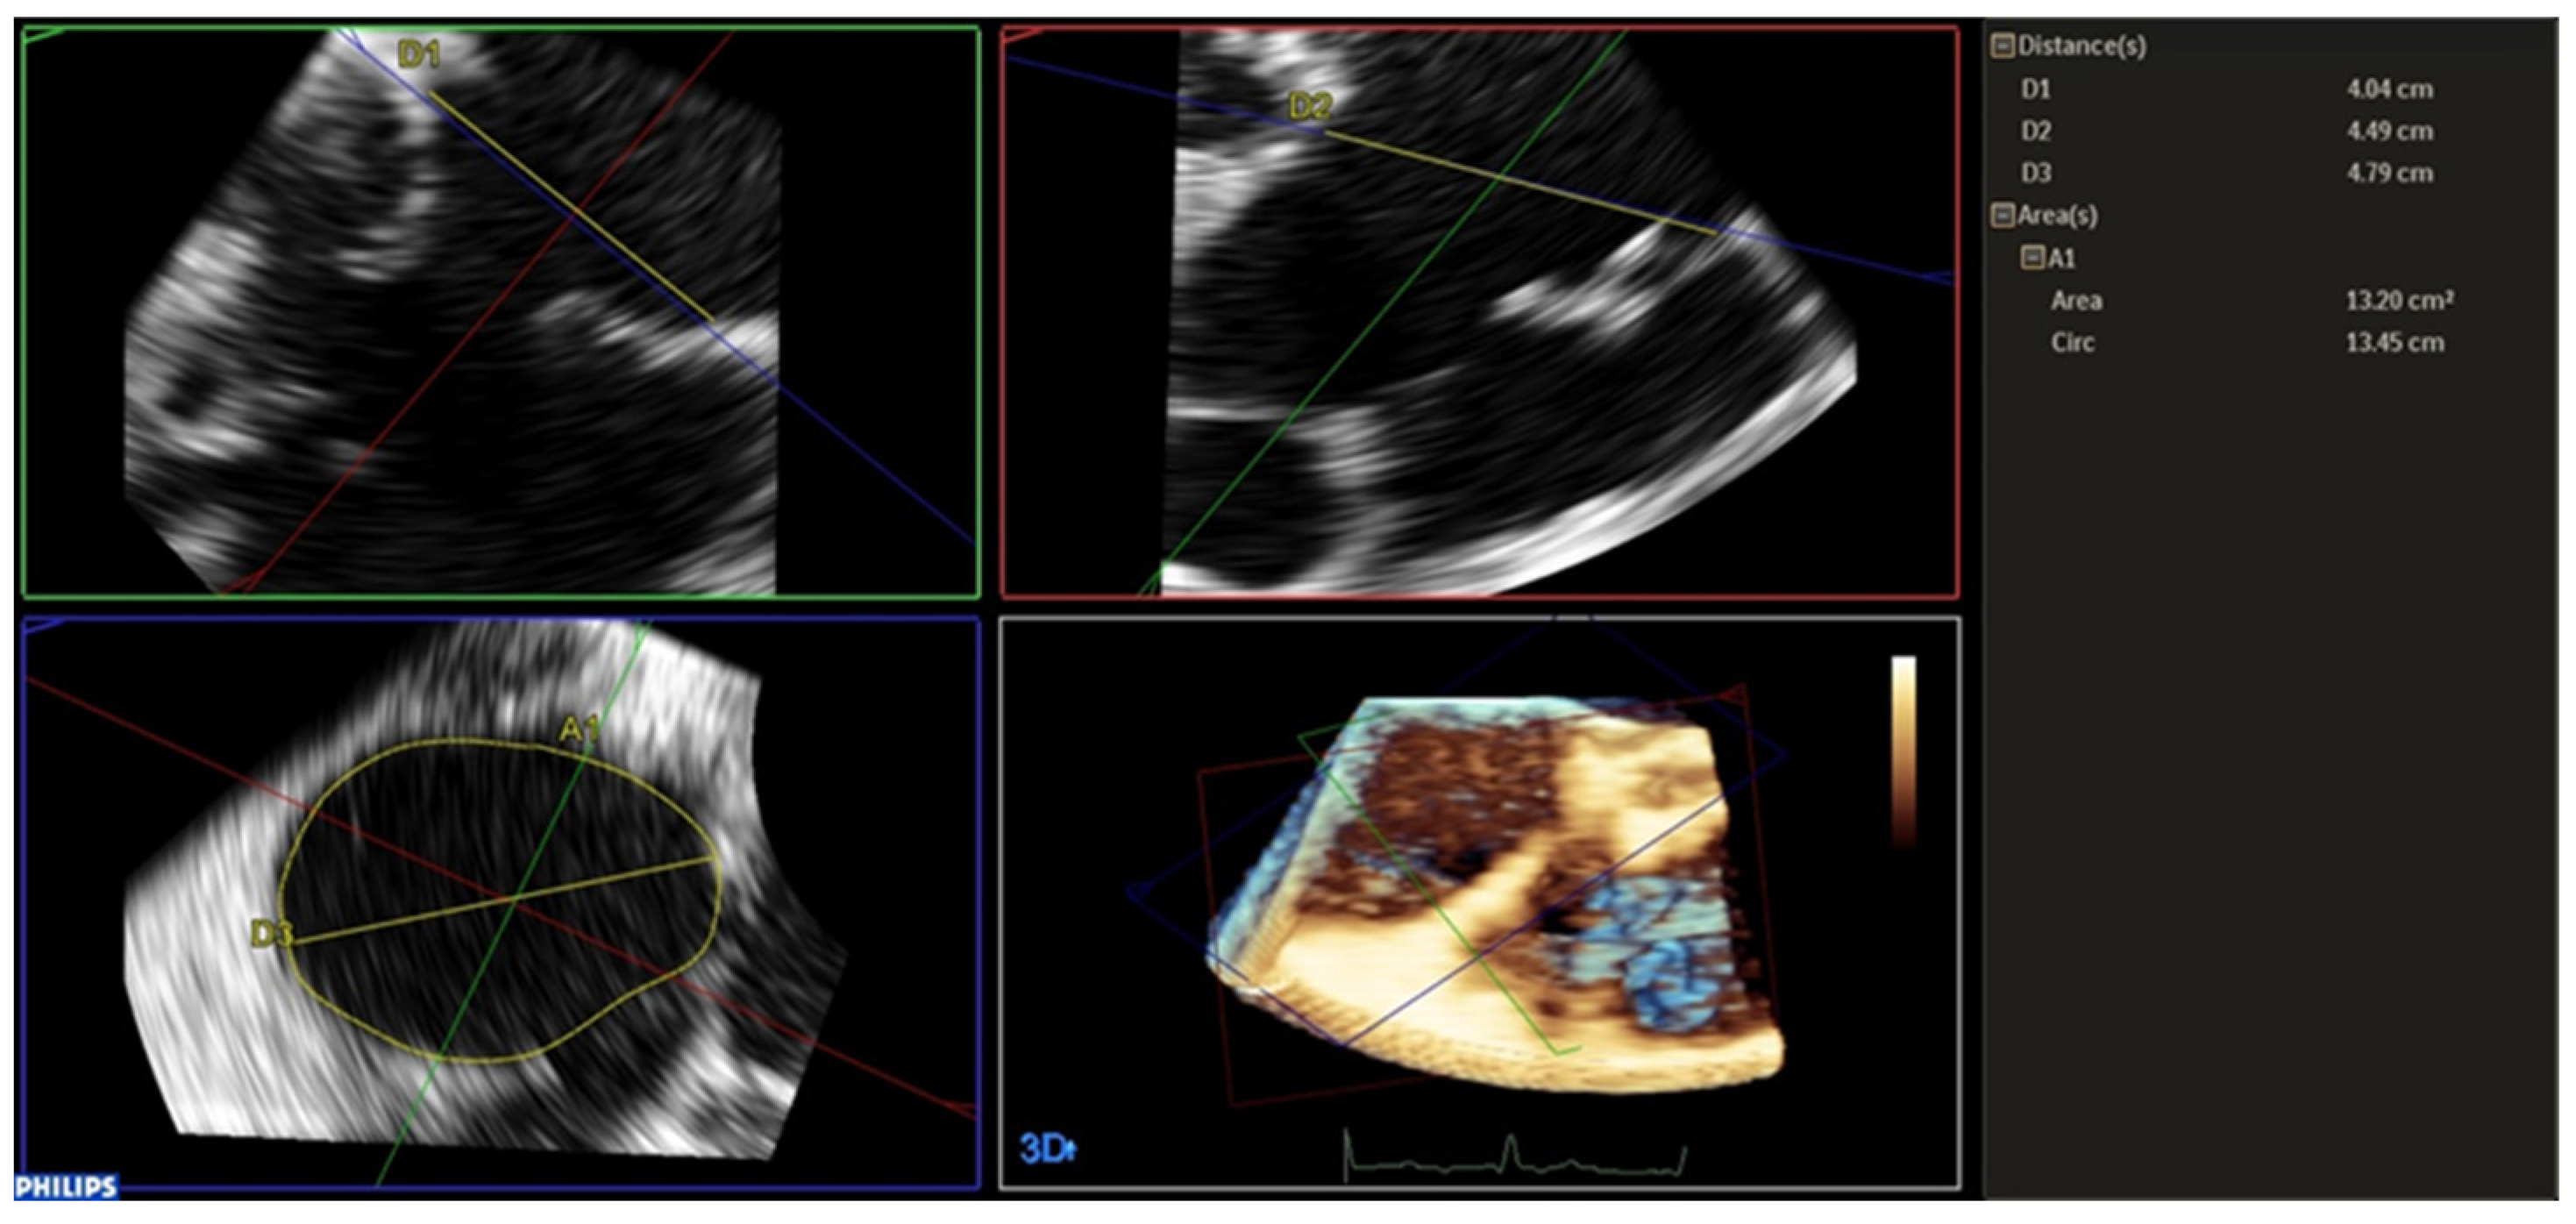

2.3. Tricuspid Annulus Analysis

| Parameters | Before | After | p Value |

|---|---|---|---|

| SL diameter (cm) | 4.09 ± 0.44 | 3.54 ± 0.53 | <0.0001 |

| AP diameter (cm) | 4.29 ± 0.79 | 4.01 ± 0.62 | 0.0626 |

| Major diameter (cm) | 4.65 ± 0.63 | 4.28 ± 0.65 | 0.0002 |

| Area (cmq) | 14.00 ± 2.91 | 11.25 ± 2.91 | <0.0001 |

| Perimeter (cm) | 13.62 ± 1.43 | 12.42 ± 1.62 | <0.0001 |

| Eccentricity Index | 0.98 ± 0.17 | 0.90 ± 0.17 | 0.0286 |